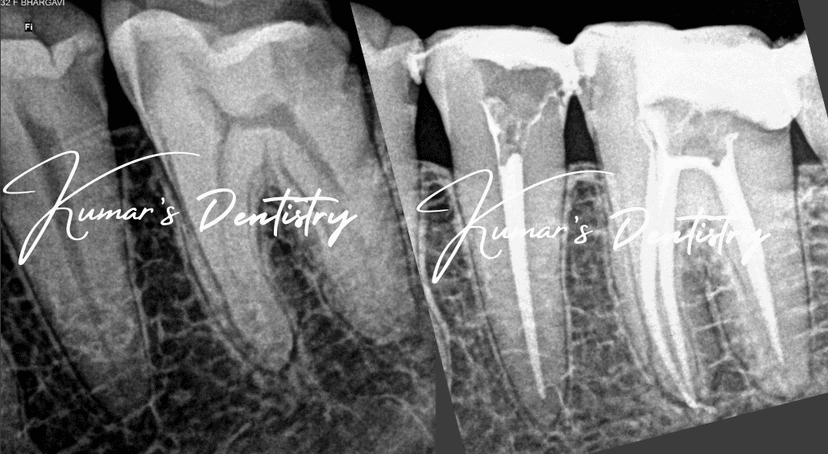

Precise root canal treatment using 25x magnification for better outcomes and faster healing